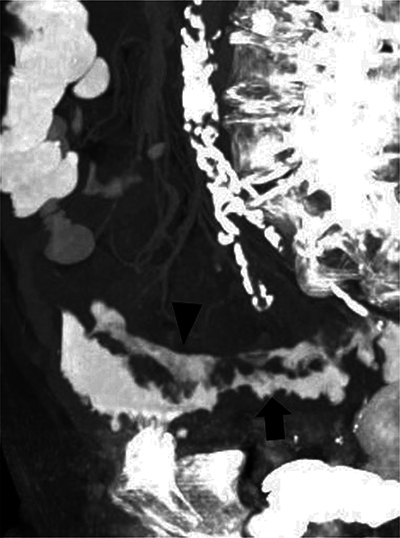

Teaching point: A longitudinal intramural fistula is a rare complication of diverticulitis that can be visualised by computed tomography (CT).